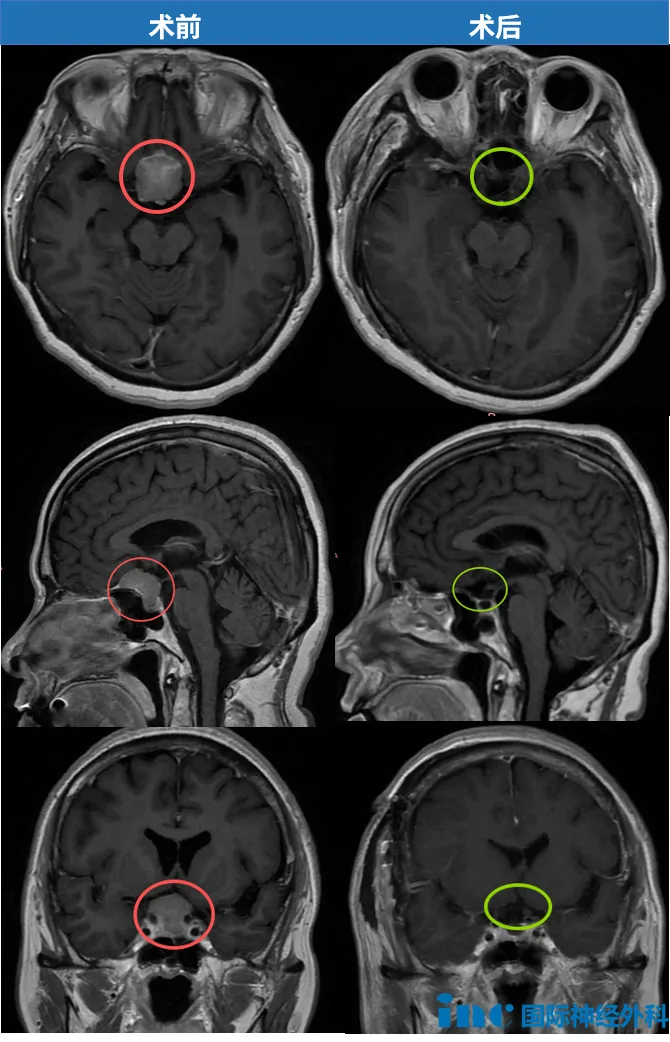

这是一场与时间的紧急赛跑:58岁患者陈女士确诊鞍区脑膜瘤,肿瘤位置险要,并已引发视力显著下降。危急时刻,为保全残余视力,家庭成员果断决策,迅速选择手术治疗;巴教授精准实施手术,成功切除肿瘤,将患者从失明边缘挽救回来。

2024年12月17日,身处国外的陈女士因面瘫和视物模糊症状,确诊为鞍区脑膜瘤。病情进展迅速,短短4天后,她紧急返回国内。详细检查显示肿瘤位于鞍底区域,尺寸约2.6cm×2.5cm。

时间持续流逝,视觉功能逐步丧失。儿子在安抚恐惧母亲的同时,积极奔走求医。2025年1月3日,他们获得巴教授关键评估意见:"手术非常紧急!"此时陈女士双眼视力呈进行性下降,检查结果显示双眼视力0.2(正常值1.0),双眼视野存在严重缺损。

由于肿瘤位于前颅底区域,生长于双侧视神经之间,随体积增大逐渐压迫视神经结构。此外,肿瘤位置险要,已波及垂体及垂体柄区域。

"一切顺利!"巴教授挽救岌岌可危的视力功能

术后当日,陈女士在ICU已能与教授流畅交流,视力部分恢复,并于当天转至普通病房。这场时间赛跑,他们最终获胜。